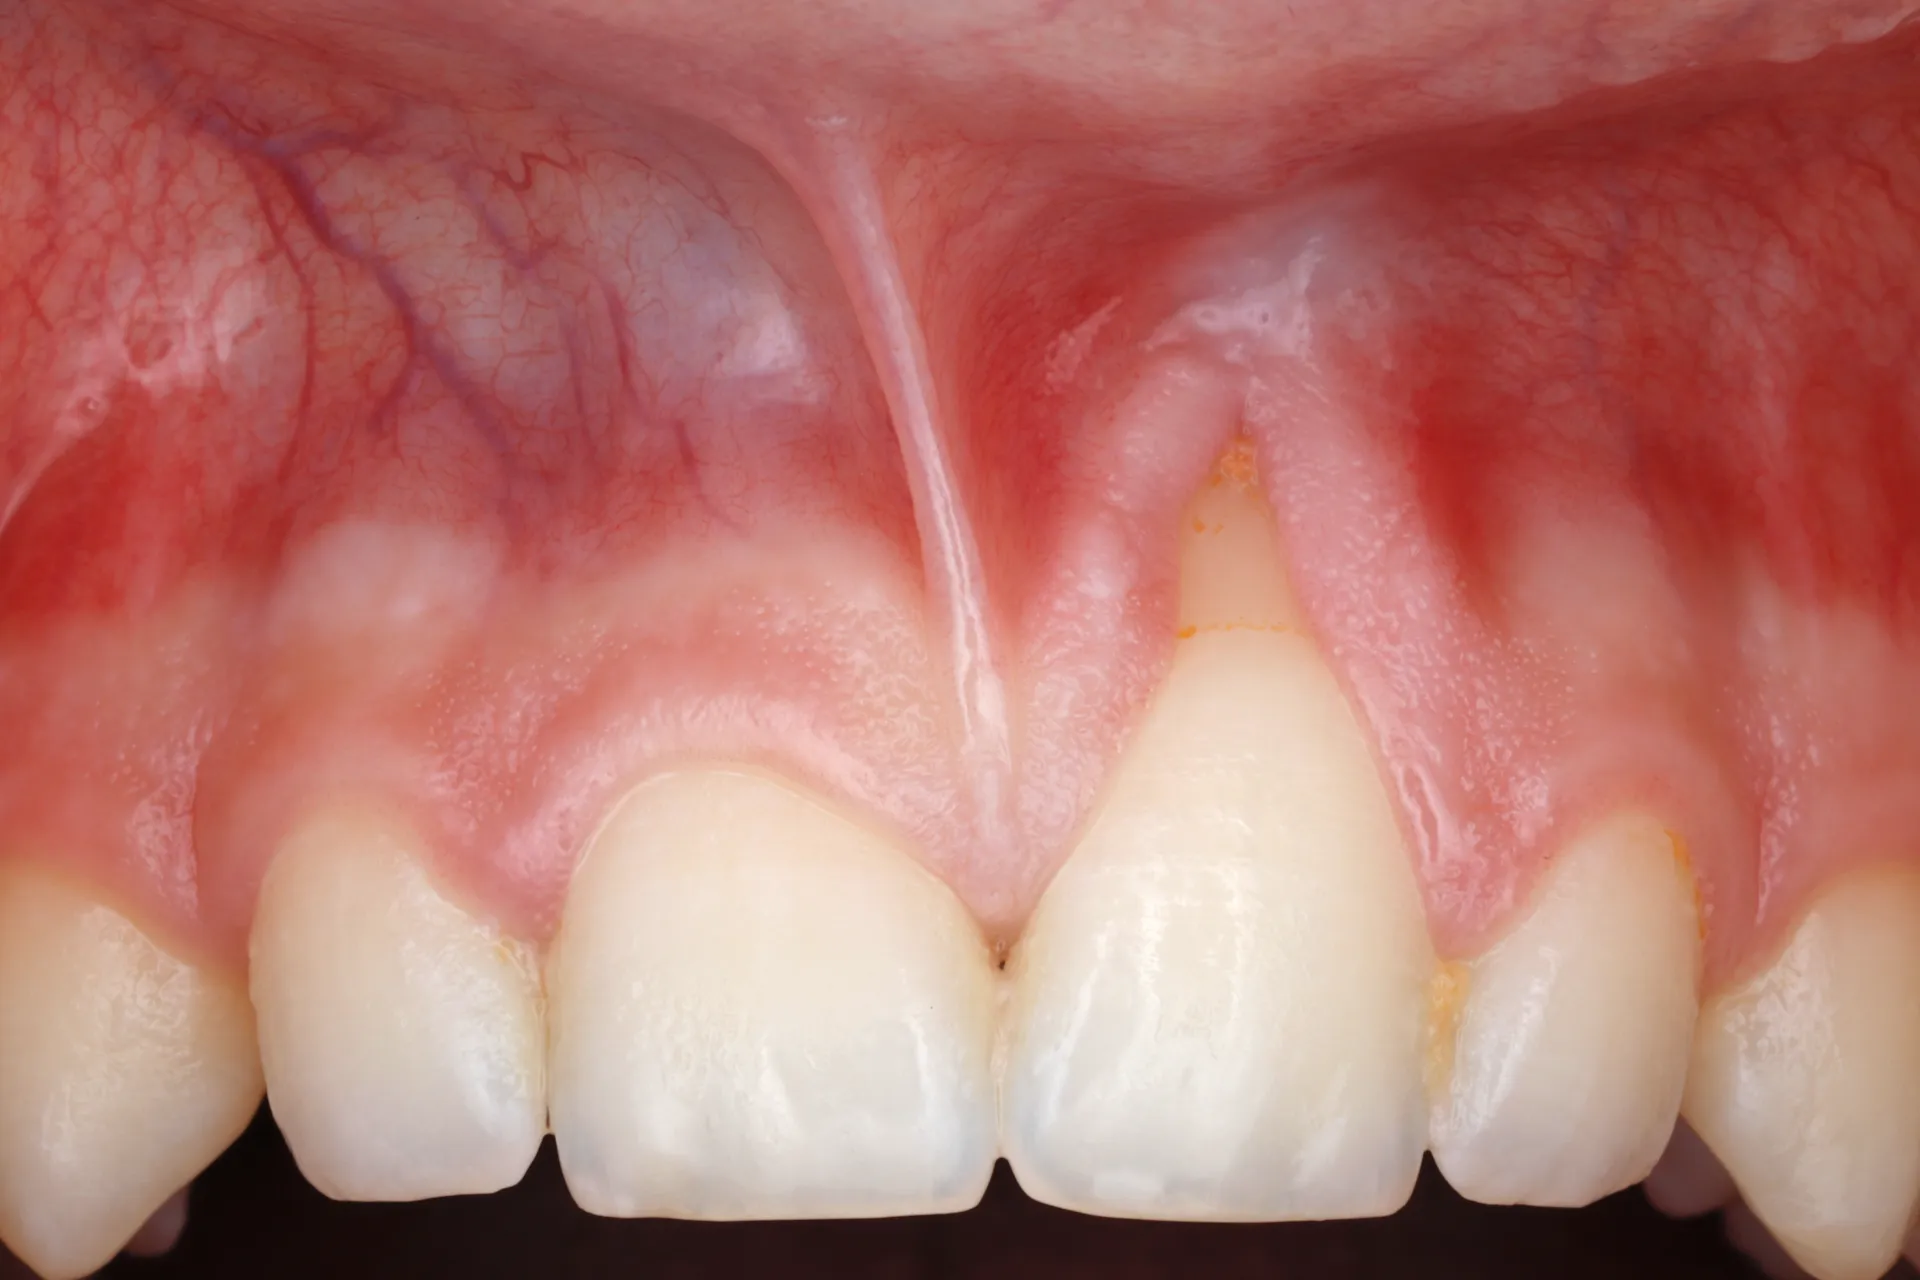

Gum Recession

Gum Grafting